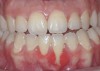

CASE 3 Fig 6. Post-orthodontic Miller Class II recession recommended for orthodontic treatment. Clinical view 5 years after orthodontic treatment showing a buccally displaced root of the lower incisor.

Figure 6

Fig 7. The CBCT sagittal view shows 4 mm tickness of bone on the lingual aspect of the affected tooth.

Figure 7

Fig 8. During orthodontic treatment showing a significant decrease of defect size.

Figure 8

In cases in which adequate lingual bone thickness (≥2.5 mm) is measured on CBCT, orthodontic retreatment should be encouraged (Figure 6 through Figure 8). Most of these patients present with a fixed orthodontic retainer bonded on the lingual aspect of the lower teeth. Therefore, the crown of the affected tooth is splinted and aligned relative to the adjacent teeth, while only the root is displaced toward the labial alveolar plate. Consequently, the orthodontic movement should consist of lingual root torque around a center of rotation placed in the crown. The torque can be easily achieved with rectangular wires or torqueing springs inserted underneath a heavy round base arch, which provides anchorage from the neighboring teeth.